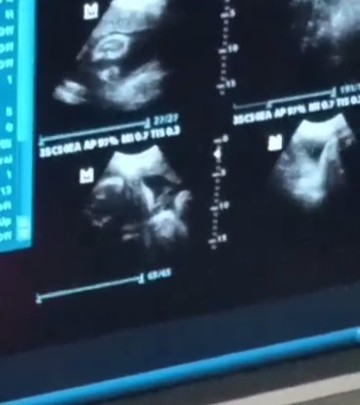

BPS RESULT

Thank you Lord, all good and healthy si baby sa kanyang bps. Bilog na bilog ang mukha. ❤️🙏